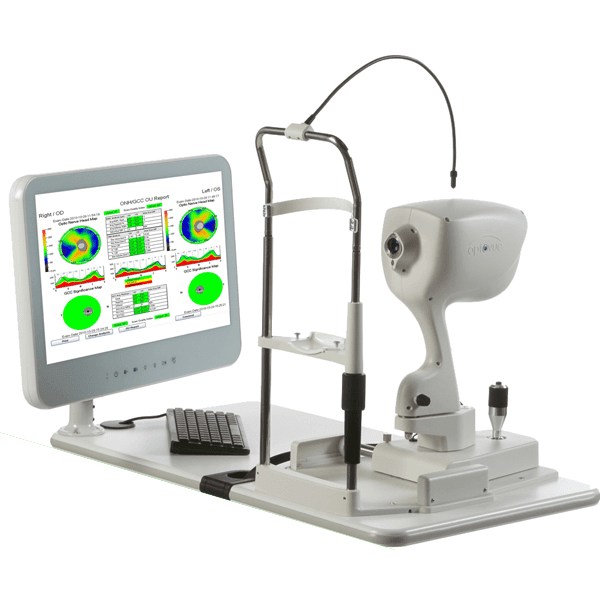

OCT..the diagnostic tool for diseases of retina

Optical coherence tomography (OCT) is a non-invasive imaging test. OCT uses light waves to take cross-section pictures of your retina.

With OCT, your ophthalmologist can see each of the retina’s distinctive layers. This allows your ophthalmologist to map and measure their thickness. These measurements help with diagnosis. They also provide treatment guidance for glaucoma and diseases of the retina. These retinal diseases include age-related macular degeneration (AMD) and diabetic eye disease,vascular occlusions as discussed above.

What happens during OCT?

To prepare you for an OCT exam, your ophthalmologist may or may not put dilating eye drops in your eyes. These drops widen your pupil and make it easier to examine the retina.

You will sit in front of the OCT machine and rest your head on a support to keep it motionless. The equipment will then scan your eye without touching it. Scanning takes about 5 – 10 minutes. If your eyes were dilated, they may be sensitive to light for several hours after the exam.